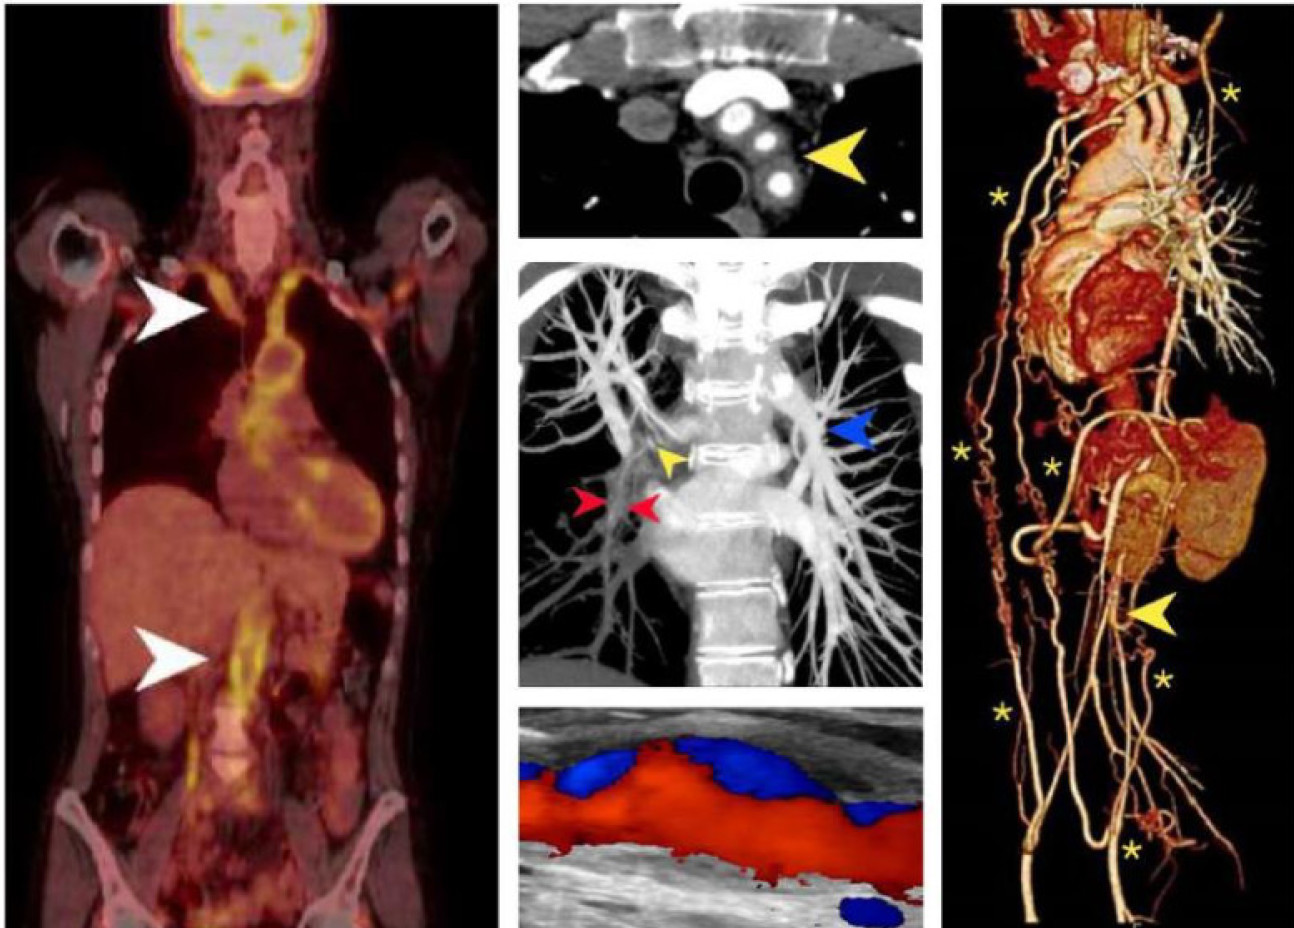

In a paper recently published in JACC Cardiovascular Imaging, we presented a series of images which summarise the various imaging modalities utilised in the management of Takayasu’s arteritis (TA)—a rare autoimmune vasculitis which affects the aorta and its major branches. Immunosuppressive therapy is employed to suppress inflammation, to prevent arterial injury and encourage positive remodelling. These images represent the 20-year cumulative experience of the multidisciplinary team at Imperial College NHS Trust treating this rare disease.

The natural history of TA is apparent through these images as we outline its diagnosis, extent and pattern, monitoring, and long-term outcomes. Early diagnosis can be facilitated with positron-emission tomography, magnetic resonance imaging (MRI) / angiography (MRA), computed tomography angiography, and high-resolution ultrasound. Furthermore, MRI and MRA remain invaluable for interval monitoring for treatment responses and promptly detecting signs of disease progression without ionising radiation. Other specialised imaging modalities are occasionally useful such as Tc99m-DSMA radionucleotide scanning to determine differential renal function in those with renal artery stenosis, and Tc99m HMPAO SPECT imaging to assess cerebral perfusion for those presenting with cerebral ischaemia, respectively. Integrated non-invasive imaging has transformed the approach to TA allowing for optimised clinical care in this patient cohort.

A. FDG-PET/CT imaging demonstrates intense homogenous tracer uptake throughout the vessel wall, consistent with aortitis and subclavian arteritis (arrows).

B. Supra-aortic artery arteritis, with cuffing of the great vessels by inflammatory tissue, is shown here by Computed tomography (CT) angiography.

C. Pulmonary artery involvement is seen in up to 50% of TA patients. This CT pulmonary angiogram demonstrates severe stenosis of the right lower lobe pulmonary artery (red and yellow arrows).

D. This high-resolution ultrasound image with colour Doppler reveals concentric, homogenous thickening of the common carotid artery wall with evidence of focal arterial wall dilatation and disturbed blood flow.

E. Tissue ischemia may be an important driver for collateral artery formation which can significantly reduce ischemic symptoms. The thoracic MRA 3D volume-rendered reconstruction shows extensive disease of the aorta culminating in distal occlusion (arrow) and extensive collaterals (asterisks) which revascularise the gastrointestinal and the lower limb circulation.